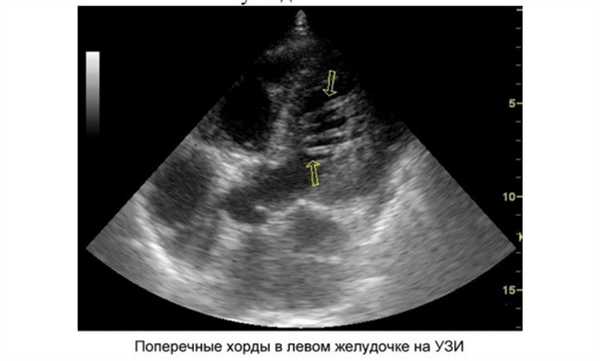

Когда врач говорит, что у вашего ребенка сердечный шум, это не повод для паники. Состояние не требует неотложных реанимационных мероприятий и интенсивного лечения. Главным диагностическим методом является ультразвуковое обследование. Оно поможет уточнить локализацию и количество добавочных тяжей. Различают следующие виды ДХЛЖ:

- по месту расположения в желудочке - верхушечные, средние, базальные;

- по отношению к оси сердца - диагональные, продольные, поперечные;

- по числу — единичные и множественные.